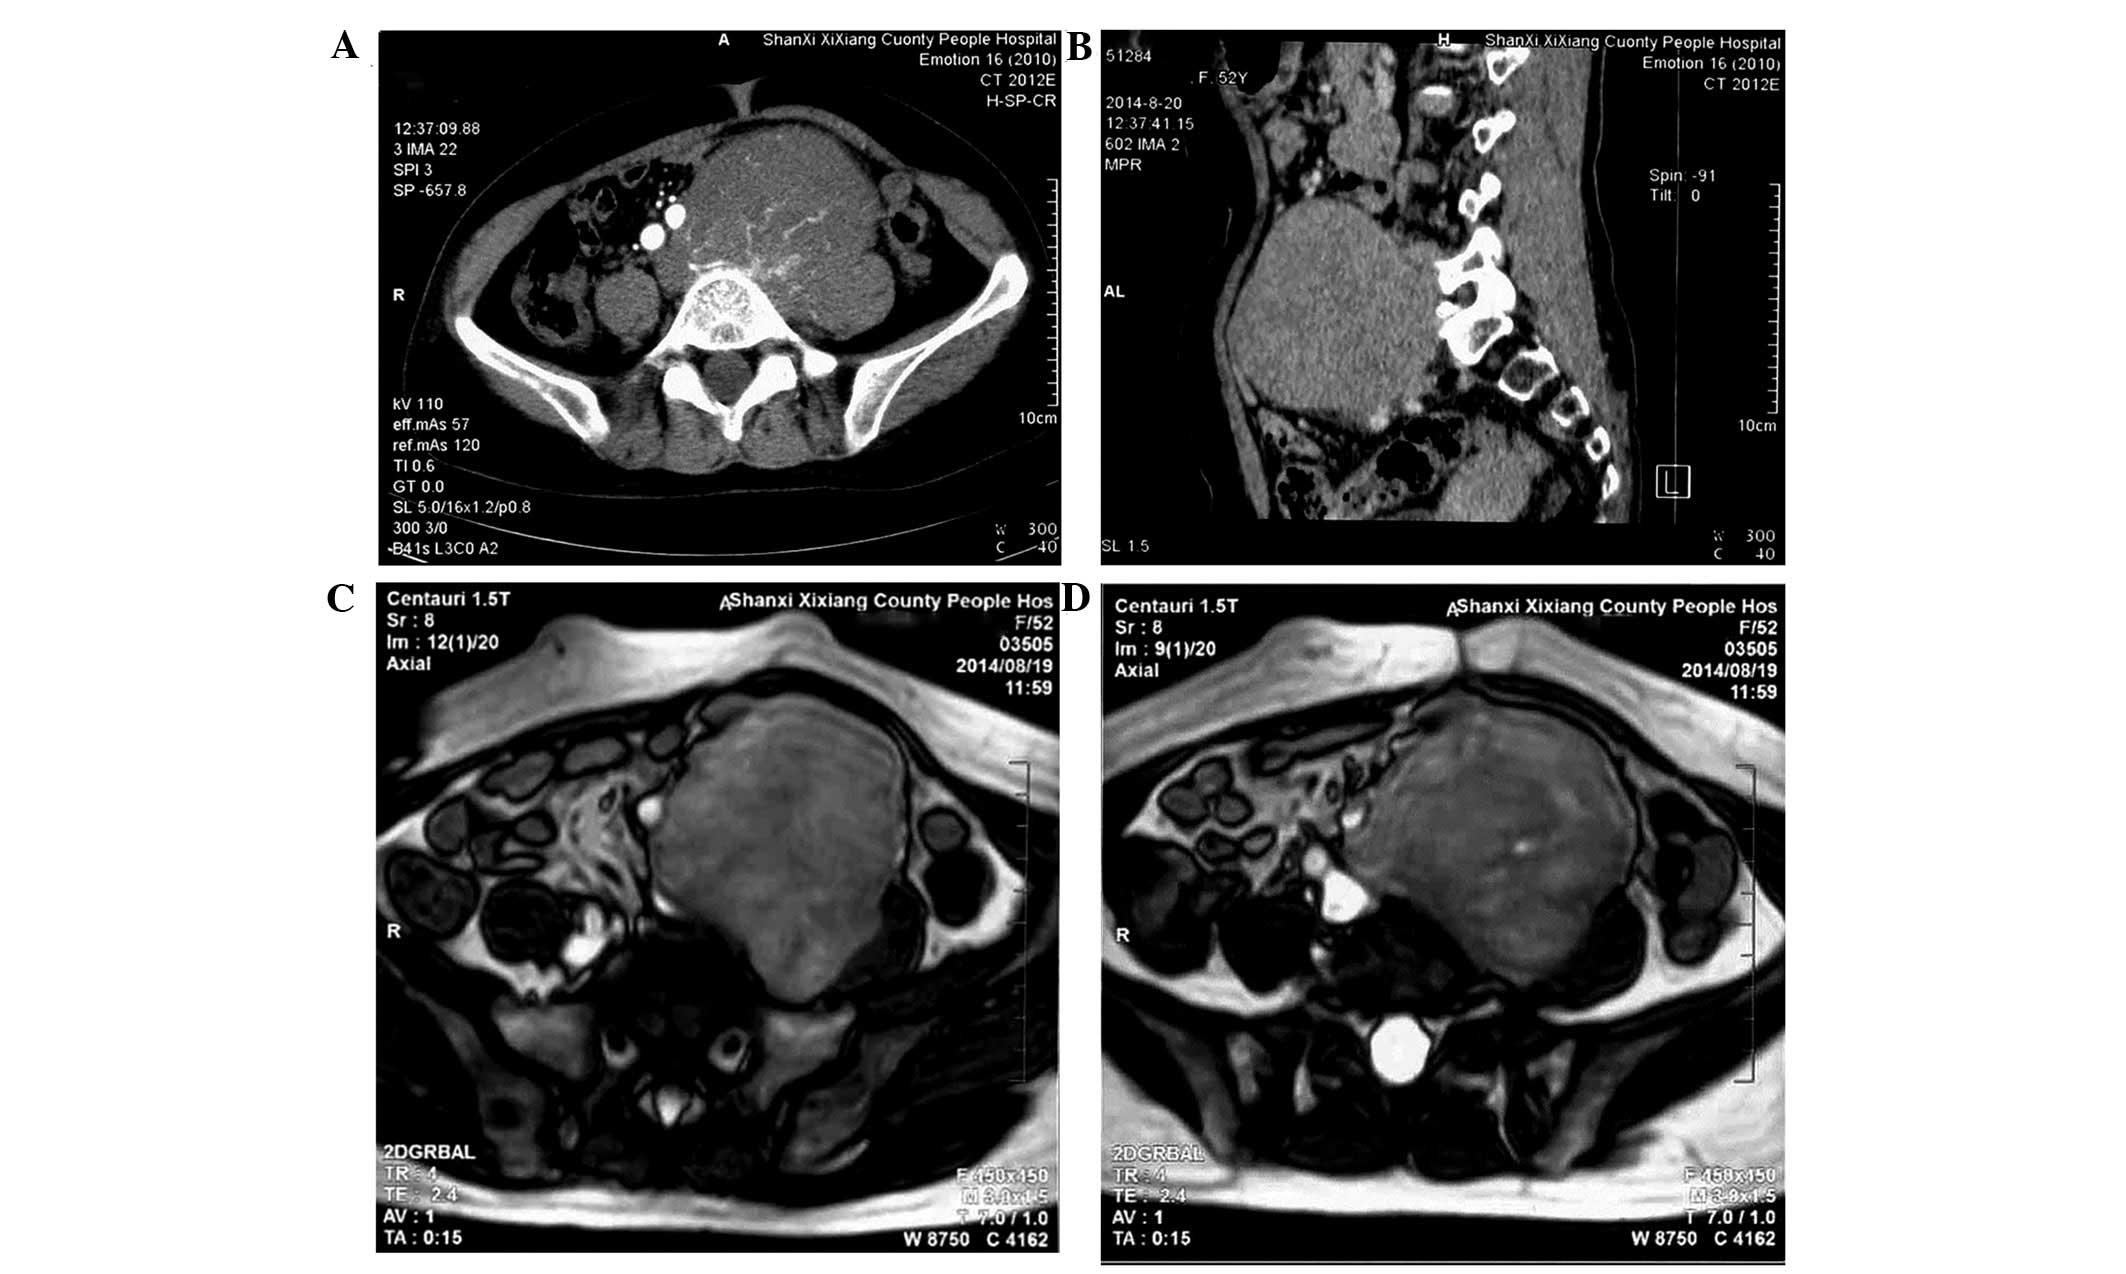

A 52-year-old woman presented to a local hospital (Shaanxi Xixiang County People's Hospital, Hanzhong, China) on August 19, 2014, with a 6-month history of an palpable abdominal mass in the left lower quadrant that was gradually increasing in size for 2 weeks. With the exception of the progressive enlargement of the mass, no other physical symptoms were observed. The patient had no family history of RS. Bowel and bladder function were normal. On physical examination, a large, firm, non-tender abdominal mass was palpable inferior to and to the left of the umbilicus. No lymphadenopathy was found. All vital signs, chest X-ray, hemogram, biochemical analysis and tumor marker results were normal. Computed tomography (CT; Siemens Somatom Emotion 16 CT scanner; Siemens AG, Munich, Germany) confirmed the presence of a 10×9×8-cm heterogeneous mass with a clear boundary and density lower than soft tissue in the left lower quadrant. The CT value was 36 Hu. During the arterial phase, multiple rete vasculums were observed in the lesion (Fig. 1A); these vasculums aggregated in the venous phase (Fig. 1B). Equal or low signal intensity was observed on T1-weighted MRI, and mixed high signal intensity was identified on T2-weighted MRI (Centauri 1.5T; AllTech Medical Systems, Chengdu, China). The vessels close to the tumor had been oppressed and shifted by the tumor. The surrounding fat gap of the tumor was clear (Fig. 1C and D). The patient was diagnosed with giant retroperitoneal tumor and referred to The First Affiliated Hospital, Medical School of Xi'an Jiaotong University on August 28, 2014.

Figure 1.

Abdominal CT scan revealing a 10×9×8-cm, low-density soft tissue heterogeneous mass with a clear boundary in the left lower quadrant. The CT value was 36 Hu. (A) During the arterial phase, multiple rete vasculums were observed in the lesion and (B) multiple rete vasculums aggregated uniformly in the venous phase. Magnetic resonance imaging scan showing (C) an equal or low signal on T1-weighted images and (D) a mixed high signal on T2-weighted images. (C and D) The vessels close to the tumor had been oppressed and shifted, and the surrounding fat gap of the tumor was clear. CT, computed tomography.